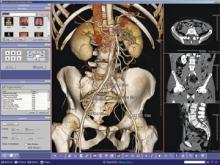

Once an emerging technology confined to early adopters, server-based advanced visualization has gradually become a more popular solution in the medical imaging informatics marketplace in the last few years. This has carried on to the point that it can today be deemed the de facto standard for advanced visualization in medical imaging enterprises.